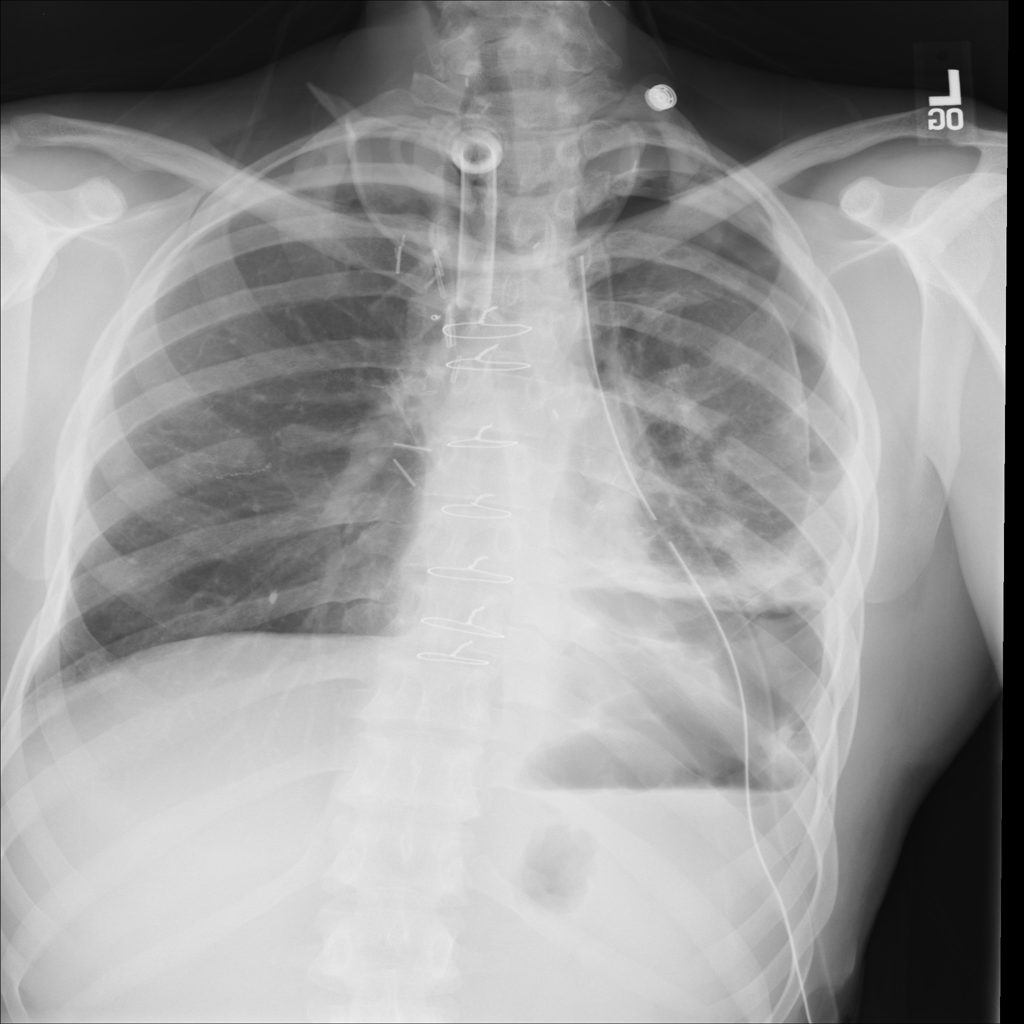

Showing up to 90 reference images for Pneumothorax.

PAT-4639 · IMG-020Pneumothorax

PAT-4639 · IMG-020

PA